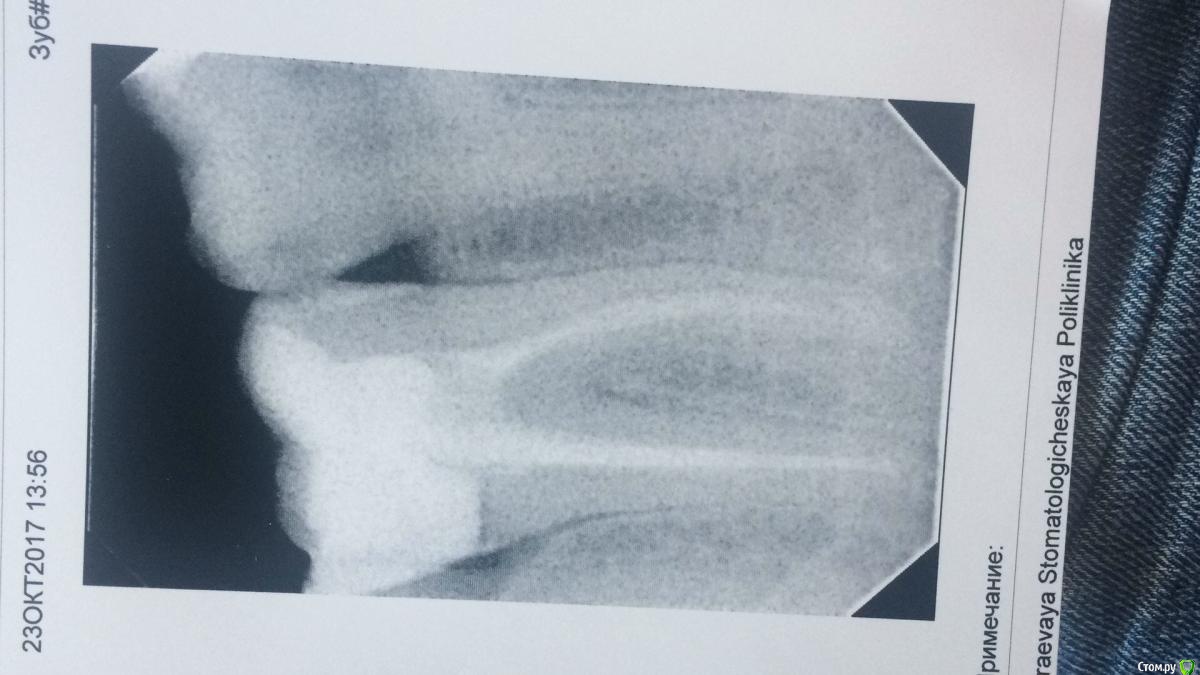

Alexey999 Опубликовано 23 октября, 2017 Поделиться Опубликовано 23 октября, 2017 (изменено) Ни с того ни с сего заболел зуб семерка. Боль при кусании и надавливании. А так же ноющая, ни спать ни вести нормальную деятельность не возможно без кетанова.Обратился к врачу, сделал снимок, сказал все в норме, у мертвых зубов часто так. Сказал воспаление между корнями и пропить антибиотик. Подскажите по снимку, стоит ли обращаться к другому врачу или пить антибиотик? Выкидывать по несколько тысяч просто за консультацию неохото.. Изменено 23 октября, 2017 пользователем Alexey999 Ссылка на комментарий

red_butler Опубликовано 23 октября, 2017 Поделиться Опубликовано 23 октября, 2017 Подскажите по снимку, стоит ли обращаться к другому врачу да 2 Ссылка на комментарий